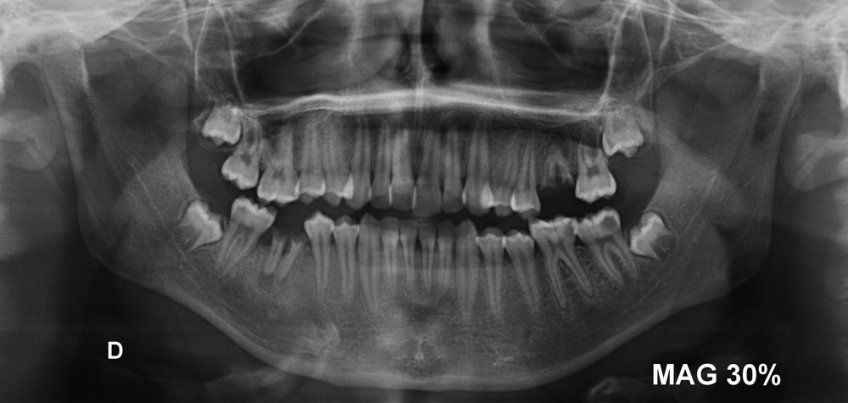

Colocación de brackets